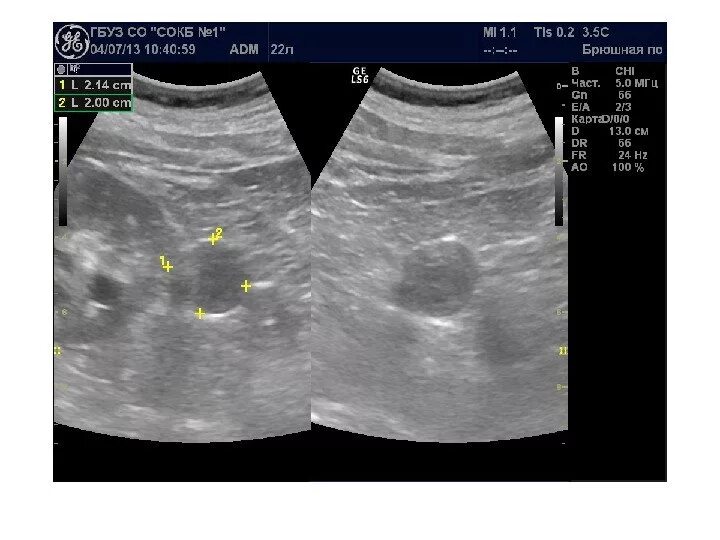

Диффузные изменения структур почечных синусов